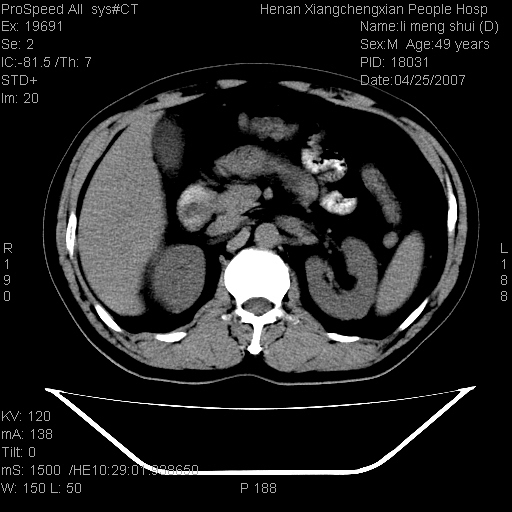

| 患者,男,49岁, 腹疼伴恶心\\呕吐20天,20天前无明显诱因出现右上腹部疼痛,钝疼,无放射,伴恶心\\呕吐,不伴发热.患者不愿增强. b超:肝脏右叶实性占位. ct:肝脏右叶可见一巨块状圆形低密度影,大小约93mm*84mm,其内可见点状高密度影,胆囊、胰腺、脾脏大小、形态及密度未见异常,腹膜后间隙未见肿大淋巴结影。 印象:肝脏右叶巨大肿块,性质待定,建议增强并穿刺活检进一步确诊。 ct平扫: ![]() ![]() ![]() ![]() ![]() ![]() ![]() ![]() ![]() ![]() ![]() ![]() ![]() ![]() ![]() ![]() ![]() 肝脏右叶肿块ct引导下穿刺活检术 患者于16时05分仰卧于ct检查台上,首先行肝脏ct扫描确定进针位置、深度、角度。在局麻下行ct引导下肝脏右叶肿块穿刺活检术。常规消毒、铺巾、局麻。在ct引导下使活检针经右侧腋中线、第9肋间隙垂直胸壁进针90mm,针头进入病变预定位置。在病变预定位置多点、多方向抽取小米样病变组织多块,涂片五张送病理检查。术后穿刺点局部无出血,未出现腹腔积液等并发症。术中及术后患者生命体征稳定,手术于17时10分成功完成。患者安返病房。 穿刺片 ![]() ![]() ![]() ![]() ![]() ![]() ![]() ![]() ![]() ![]() ![]() ![]() ![]() ![]() ![]() ![]() 病理结果肝细胞癌 ![]() 原贴地址:http://www.radinet.com.cn/forum_view.asp?forum_id=4&view_id=24130 ok |